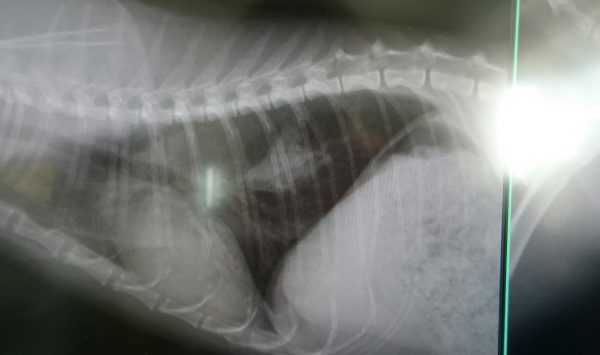

このデカ忌々しいやつがない!↓

ほうら!

どうだ!うちのおとめはすごいだろう!(σ≧▽≦)σ

「すごいですよ、どの先生が見ても、これが転移巣だとは判断がつきにくいか、分からない程です」

「いや、これはすごいですよ」